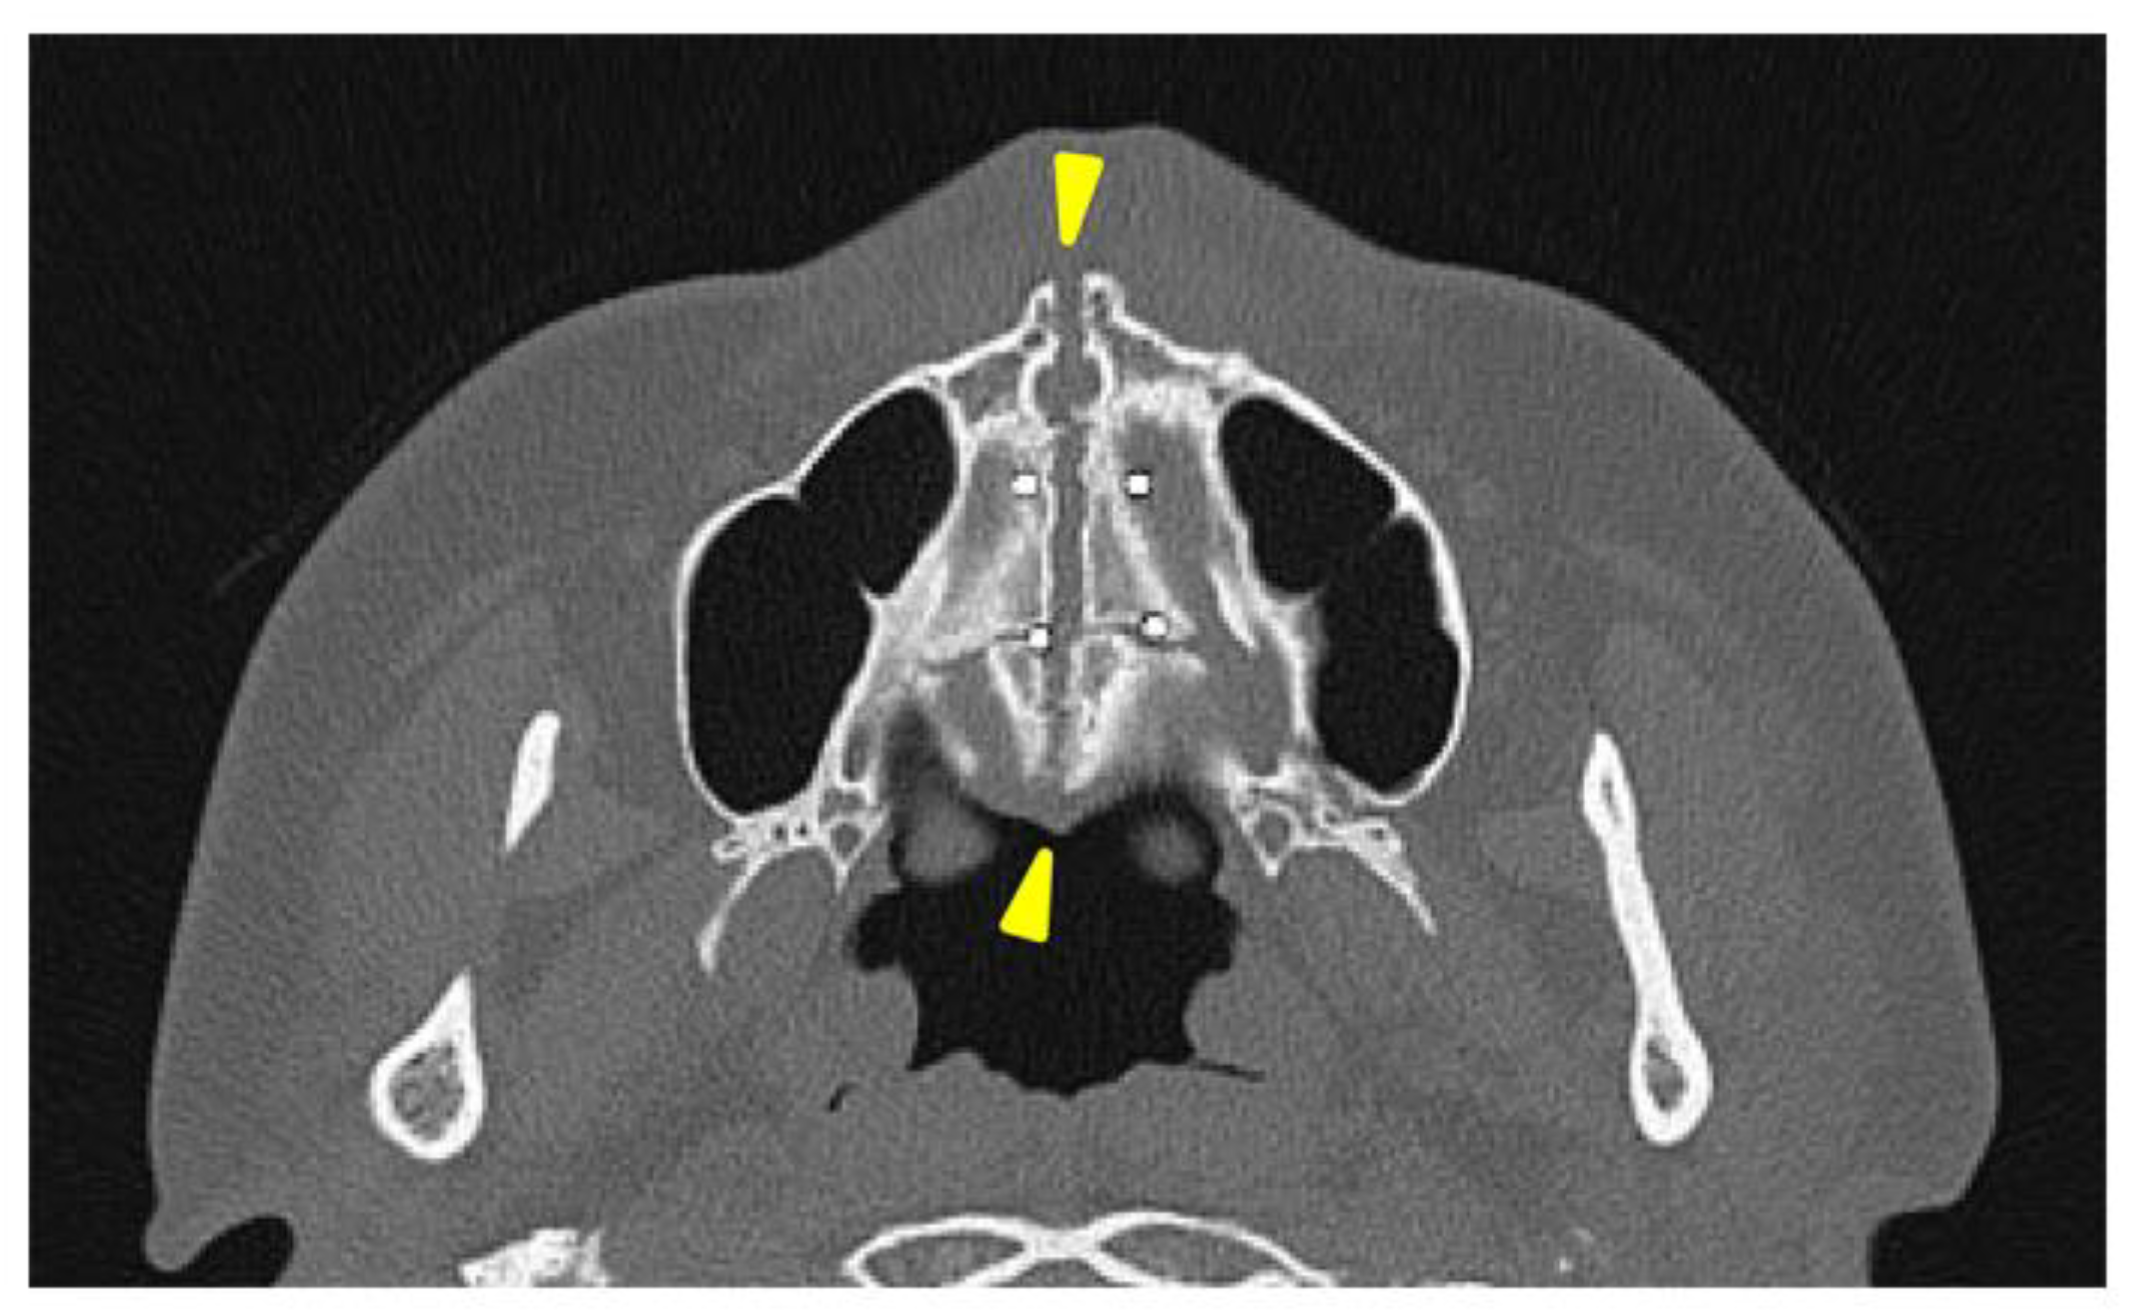

A head CT was performed on the same day. The axial slices revealed a 4-mm-wide separation of the midpalatal suture (Figure 3). A fracture of the left maxilla was also observed. The line of this fracture extended from the orbital floor and the anterior surface of the maxilla (Figure 4), starting at the medial edge of the orbital rim, passing through the entire wall of the infraorbital foramen (Figure 5a, b), and reaching the maxilla’s alveolar process. Three-dimensional CT reconstruction revealed that the rapid expansion of the maxilla had been resisted by the surrounding bones, particularly the zygomatic bones, leading to the observed fracture.

Figure 3. Axial view of the facial bone computed tomography at the level of the palatine bone.

Figure 5. Axial view of the facial bone computed tomography at the level of the intraorbital canal. (a)A fracture line passing through the infraorbital canal is observed between the two yellow triangle markers. (b) A fracture line along the infraorbital canal is observed extending posteriorly to the orbital floor (Yellow triangle marks).